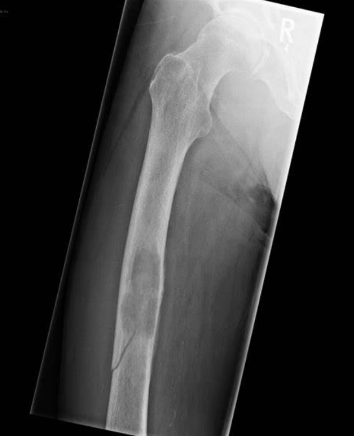

What fracture is this?

Pathologic fracture

What is a pathologic fracture?

Fracture due to disease process